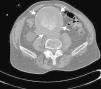

Dolor lumbar subagudo

Subacute back pain